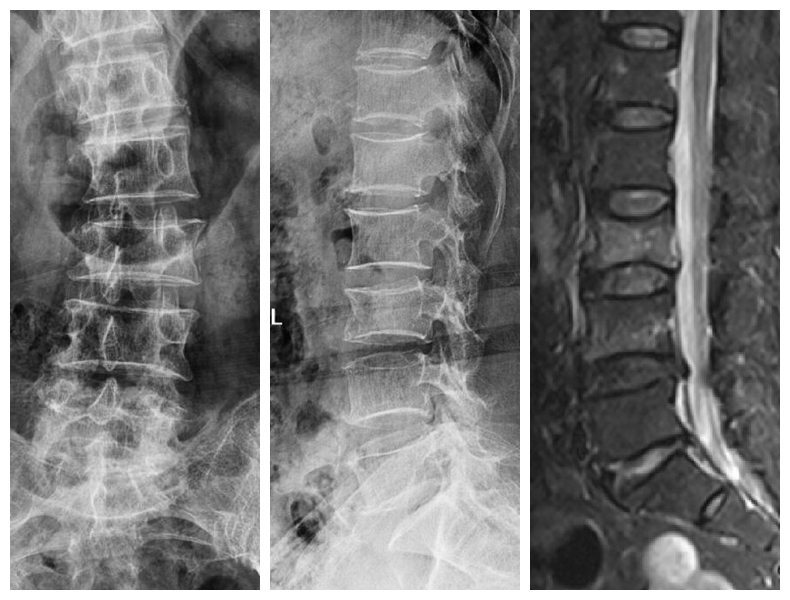

典型病例:患者**,男性,43歲,因“摔傷致胸腰背部疼痛、活動(dòng)受限2小時(shí)”門診平車入院。雙下肢肌力、感覺及肌張力正常。

本例患者術(shù)后5天在腰圍保護(hù)下獨(dú)立下床,雙下肢肌力感覺正常。